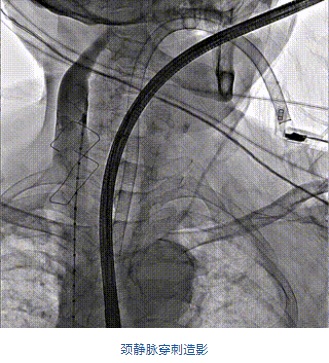

團(tuán)隊(duì)前期經(jīng)過(guò)多次討論,制定了周密的手術(shù)策略和預(yù)案。由于患者已是近九旬的超高齡老人,傳統(tǒng)外科開(kāi)胸手術(shù)風(fēng)險(xiǎn)極高,純介入經(jīng)血管三尖瓣替換能夠明顯減少創(chuàng)傷。術(shù)中陳茂及馮沅教授結(jié)合體表定位在造影指示下精準(zhǔn)穿刺右側(cè)頸靜脈并預(yù)置兩把血管縫合器。成功建立經(jīng)皮血管入路后在食道超聲和DSA的引導(dǎo)下順利完成人工瓣膜植入,術(shù)后超聲和造影顯示人工三尖瓣同軸性良好,瓣架固定牢靠,無(wú)反流和瓣周漏,平均跨瓣壓差降為1mmHg。術(shù)畢收緊預(yù)置的血管縫合器縫線完成止血,縫合效果滿意,在手術(shù)室即刻拔除氣管插管。